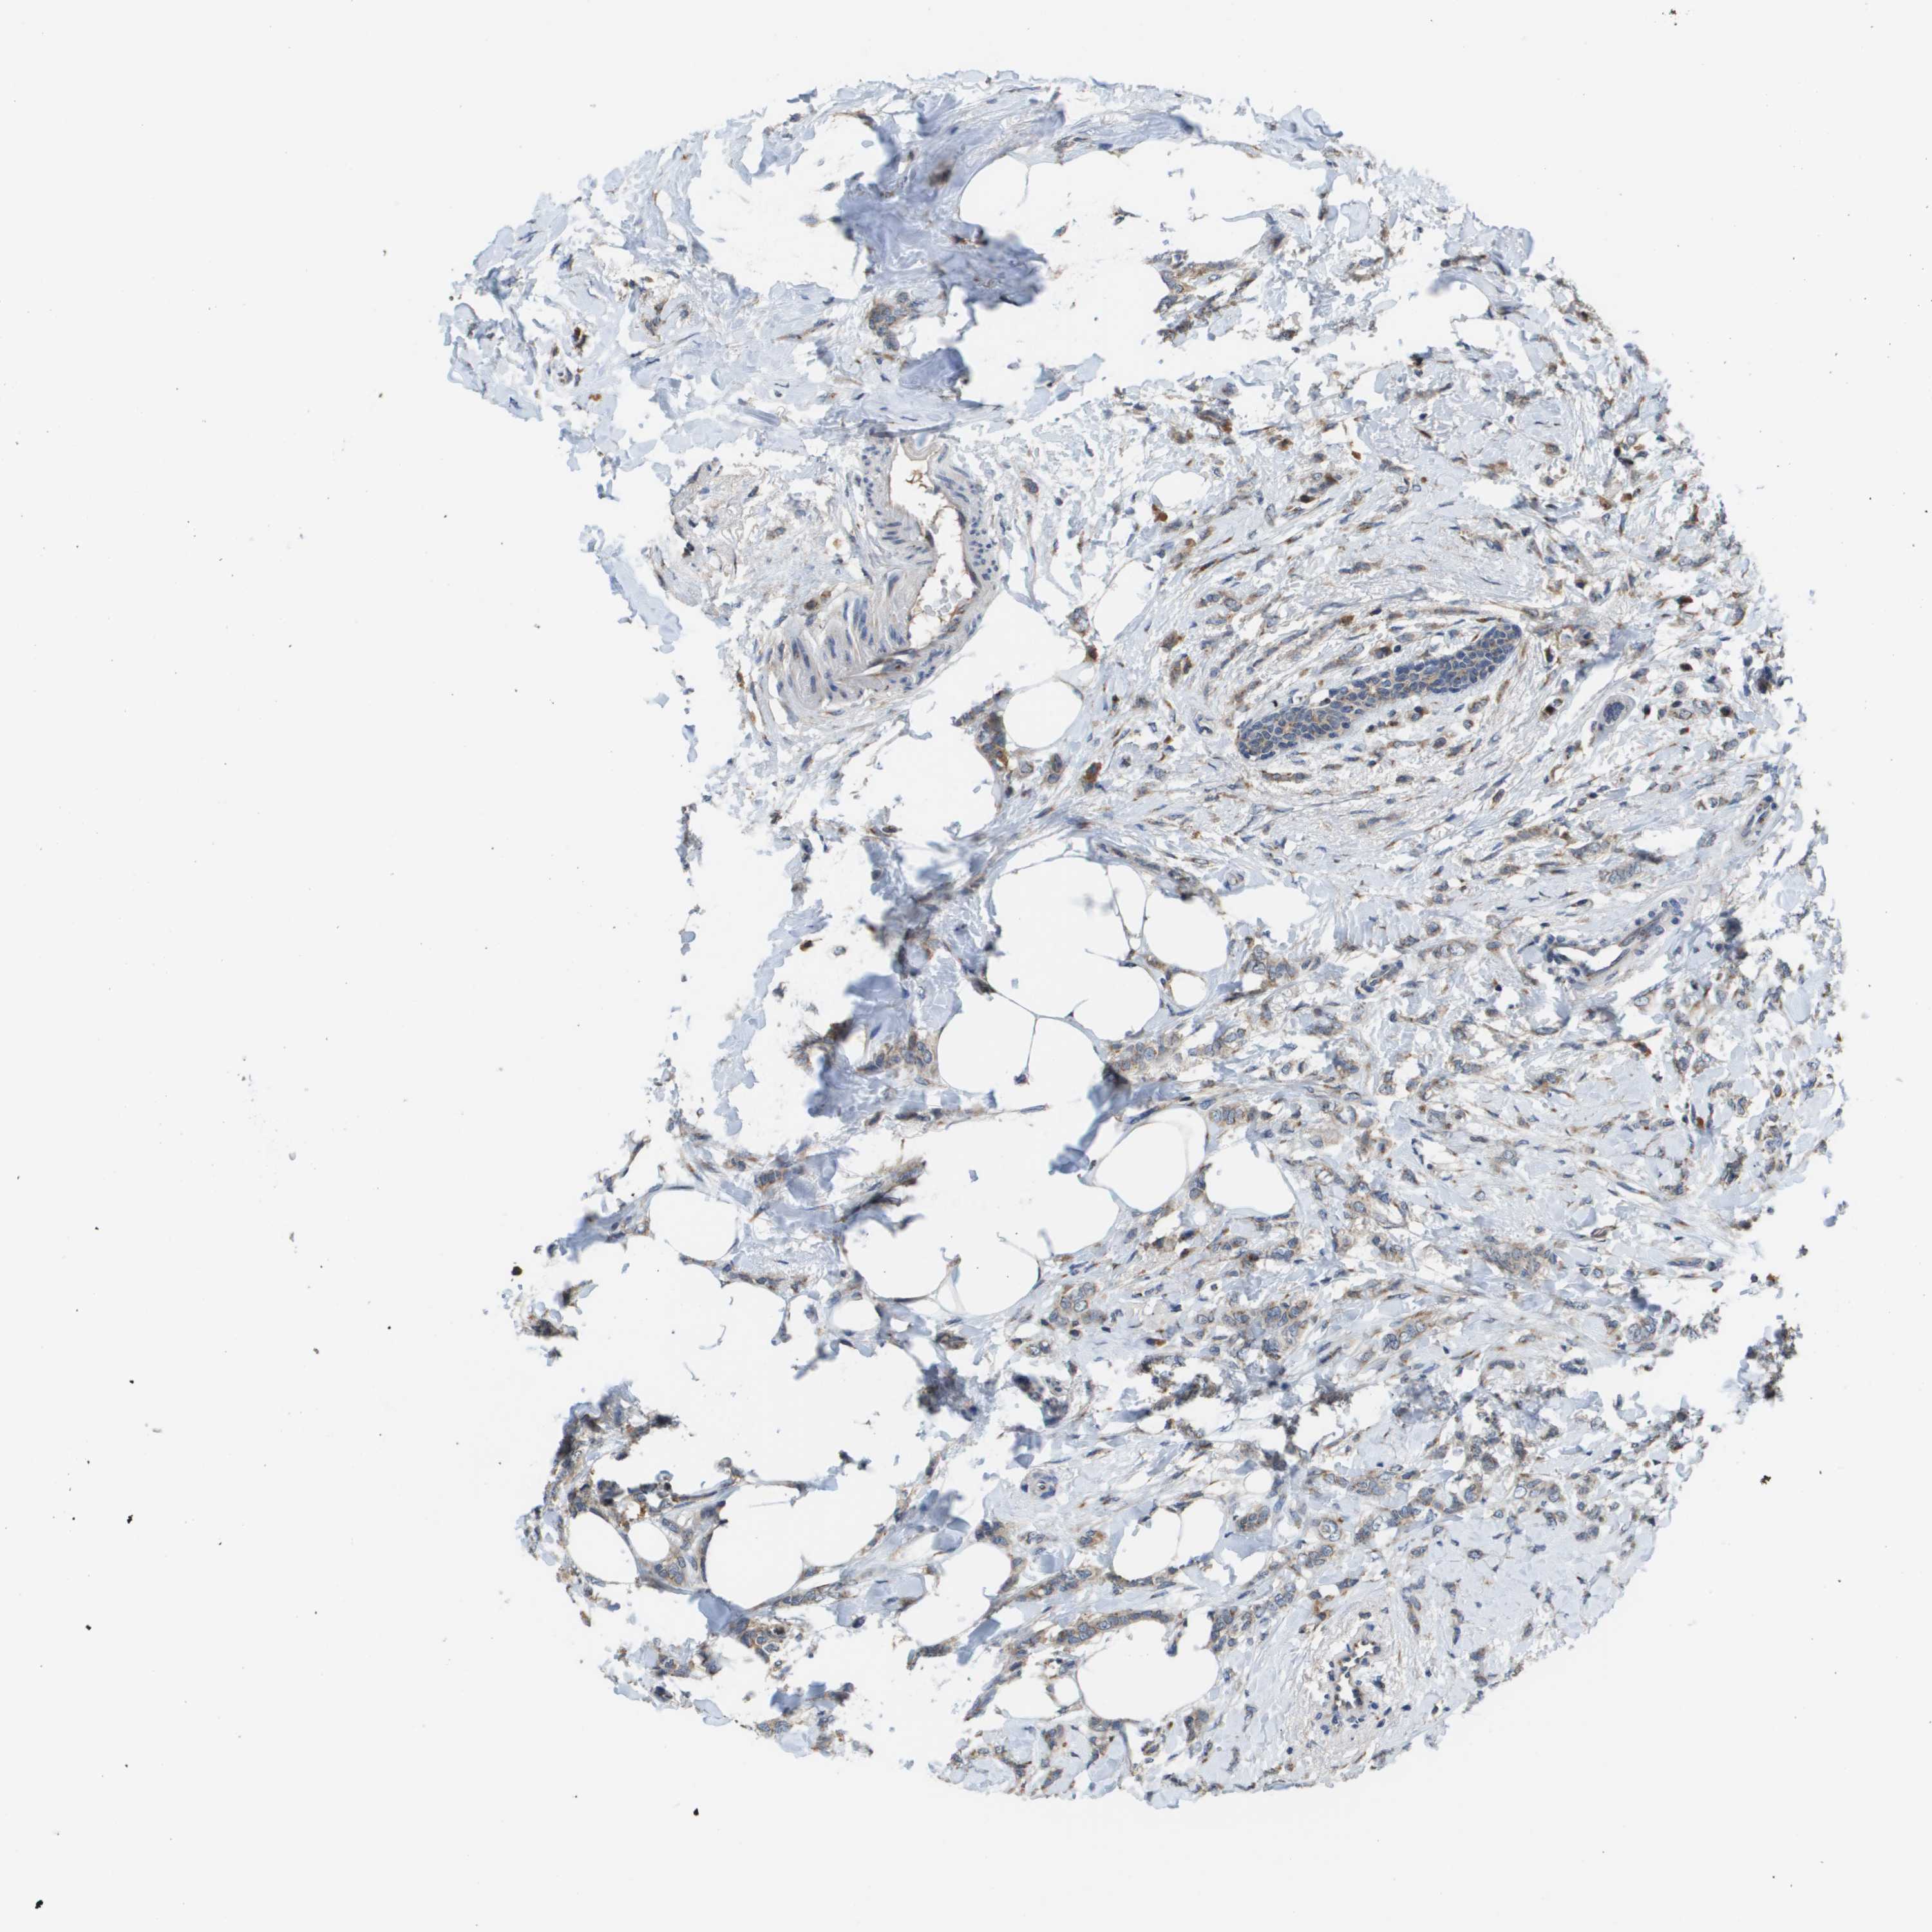

CANCER BREAST CANCER Show tissue menu

BRCA TCGA BRCA VALIDATION PROTEIN EXPRESSION